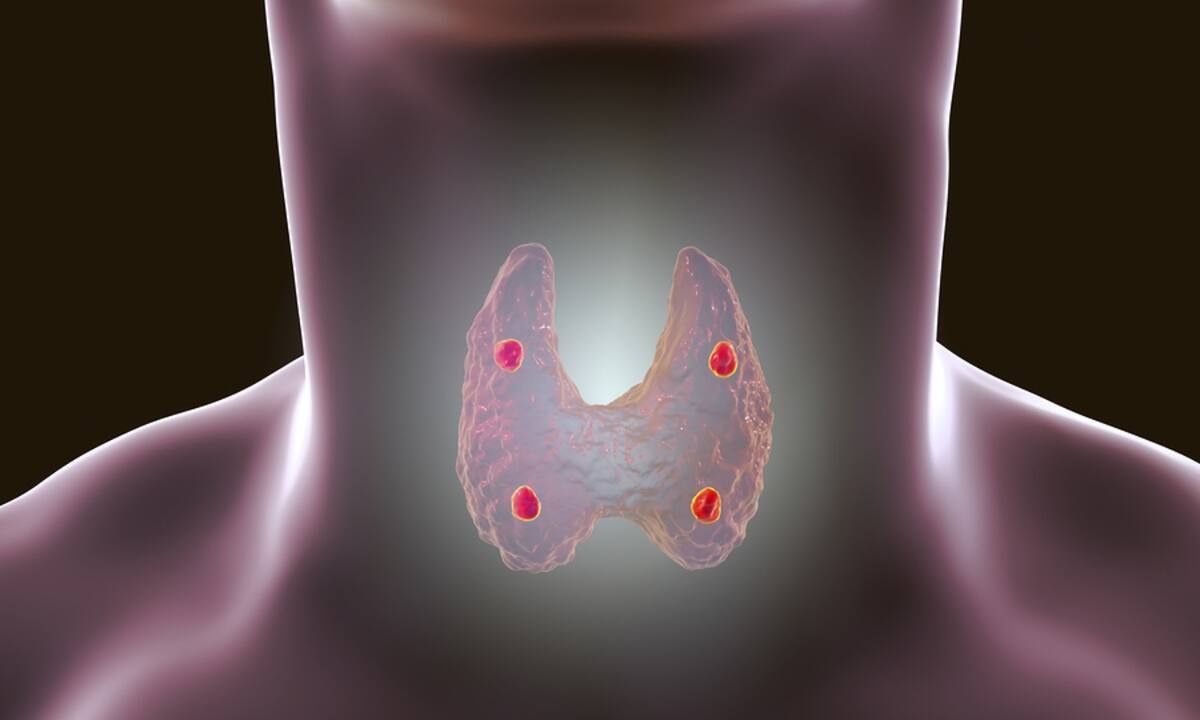

Θυρεοειδής: 13 συμπτώματα που «δείχνουν» πρόβλημα (εικόνες)

Ο θυρεοειδής, ο αδένας σε σχήμα πεταλούδας που βρίσκεται στη βάση του λαιμού, παράγει ορμόνες απαραίτητες για τον μεταβολισμό και τη λειτουργία του εγκεφάλου.

Τα συμπτώματα δυσλειτουργίας του είναι πολλές φορές ασαφή, αν όμως παρατηρήσετε ότι κάποιο από τα παρακάτω επιμένει ή έχετε πάνω από ένα, είναι χρήσιμο να συμβουλευτείτε ενδοκρινολόγο και να κάνετε αιματολογικές εξετάσεις για τον έλεγχο των επιπέδων των ορμονών του θυρεοειδούς.